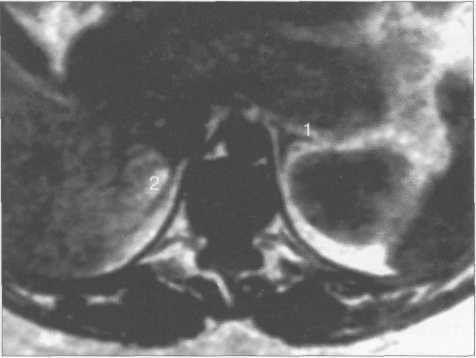

Нормальные надпочечники на Т1- и Т2-ВИ представляют собой однородные, гипоинтен-сивные структуры, которые хорошо дифференцируются на фоне окружающей жировой клетчатки (рис. 12.7). При использовании Т2-В И сигнал от паренхимы надпочечников сравним с таковым от паравертебральных мышц; незначительно превышает сигнал от печени и коркового вещества почек и значительно превосходит сигнал от ножек диафрагмы (рис. 12.8).

Рис. 12.7. МРТ надпочечников. Т1-ВИ, аксиальная плоскость.

1 —левый надпочечник; 2 — правый надпочечник.